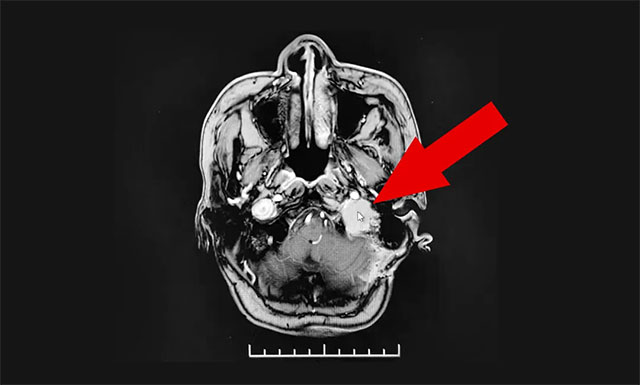

年近六旬的上海患者秦女士(化名),2010年进行右甲状腺癌切除手术。2020年6月出现头晕等症状就医,查出颅内占位病变。经诊断,考虑为甲状腺癌术后脑转移。

▲ 患者脑转移瘤病灶位置

近期,经亲友推荐,秦女士慕名来到上海蓝十字脑科医院放疗科寻求进一步治疗。王晓东主任团队根据患者的病情制定了科学合理、个性化规范化的治疗方案。在接受一个月的精准放射治疗后,患者头晕、吞咽困难等症状有不同程度的改善,近期顺利出院。